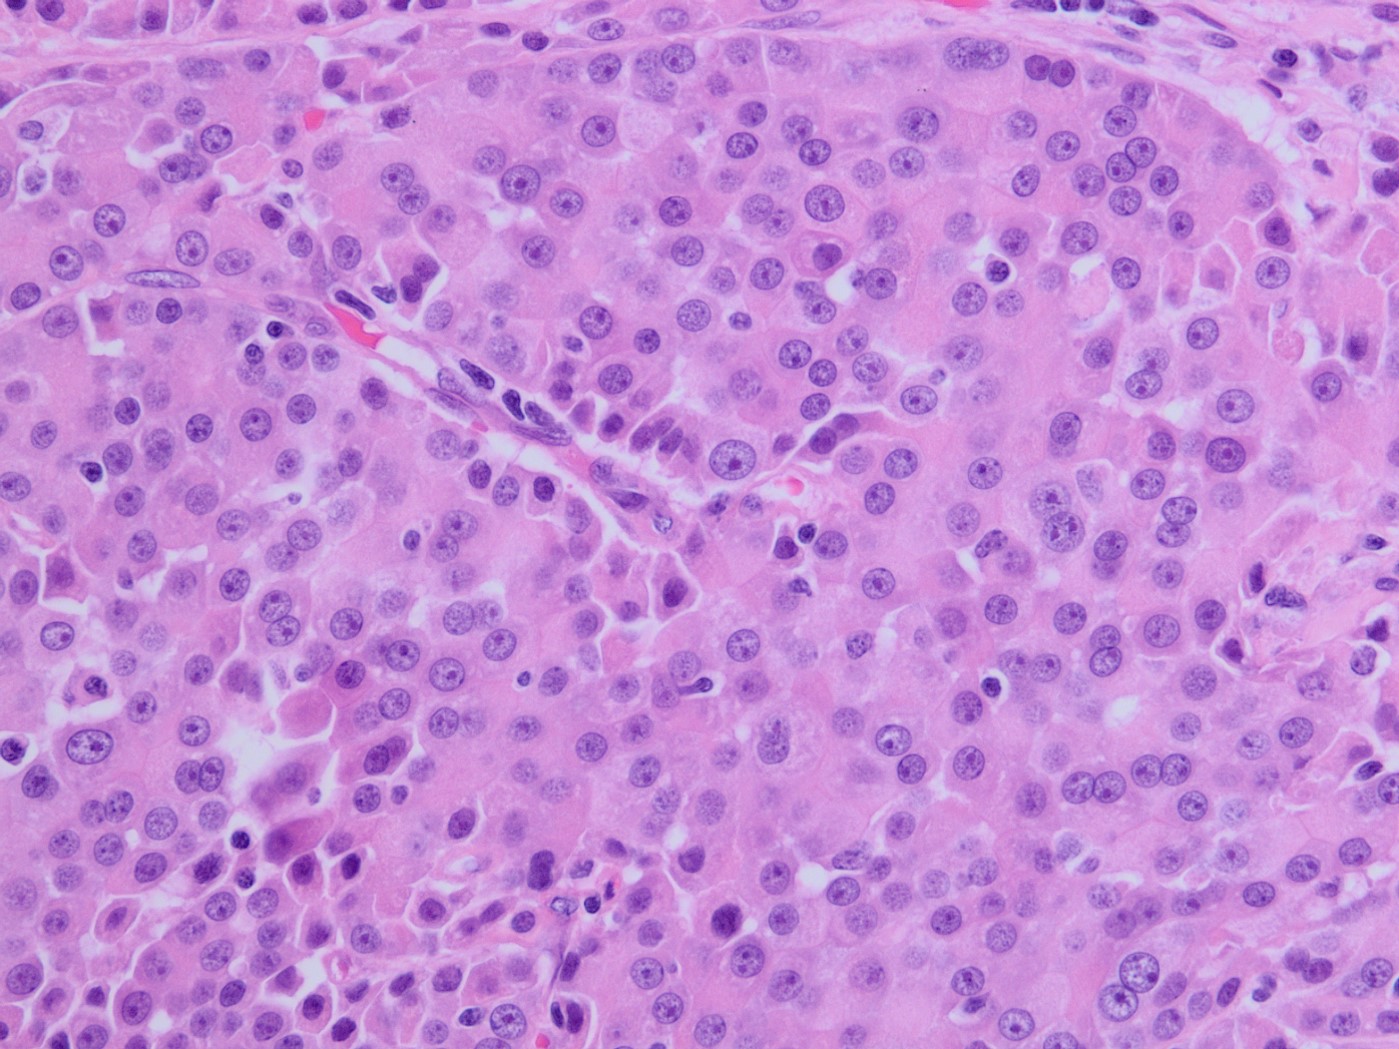

A 75-year-old woman with suspected pancreatic NET undergoes a Whipple. The morphology of the tumor is seen in Fig A-D. A synaptophysin is performed (Fig E). What additional IHC profile can be expected in this tumor?

The tumor is solid and cellular with the individual cells displaying abundant granular cytoplasm and round monotonous nuclei with prominent nucleoli, configured in a vague acinar formation. These features are consistent with an acinar cell carcinoma, therefore positive staining for trypsin and BCL10 are expected (figures).

The main differential diagnosis in this case is a well differentiated neuroendocrine tumor. However, a stain for synaptophysin stain is negative, with an islet serving as an internal control. This finding rules out a neuroendocrine tumor, therefore chromogranin would also likely be negative. Acinar cell carcinoma can sometimes have weak staining for neuroendocrine markers, however the KI67 index should be high in acinar cell carcinoma. Pancreatoblastoma is also an important differential diagnosis for acinar cell carcinoma. The background of pancreatoblastoma is often that of an acinar pattern with corresponding trypsin positivity. However, pancreatoblastoma will contain squamoid nests that show nuclear staining for beta-catenin. Solid pseudopapillary neoplasm (SPN) should also be considered as a differential, as it is a solid and cellular neoplasm with bland cytology. However, acinar cell carcinoma lacks the distinctive small capillaries and pseudo papillae formation seen in SPN. SPN will also have characteristic nuclear beta catenin staining.